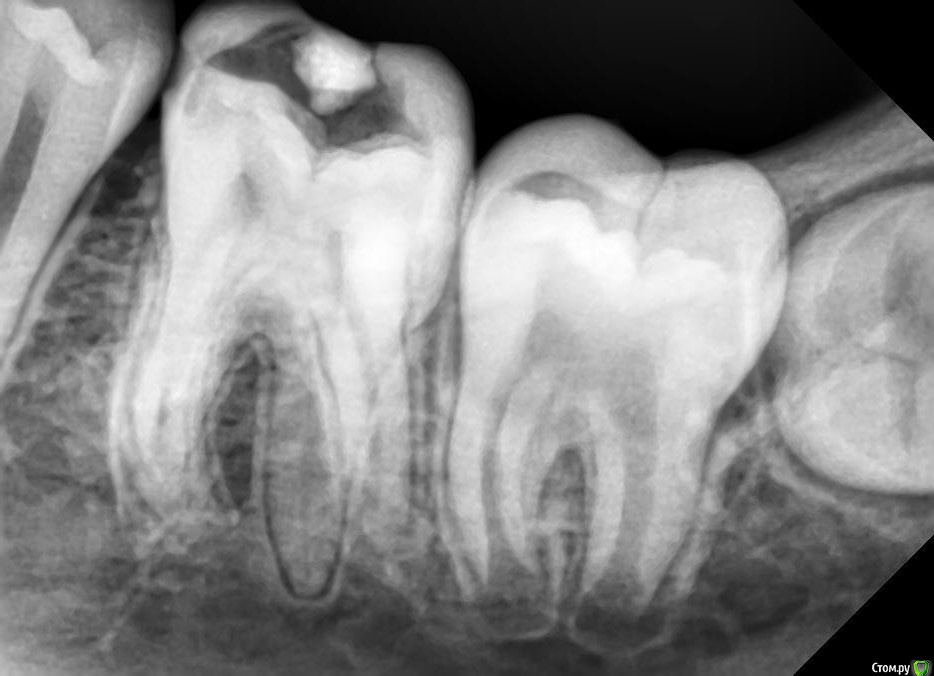

khelsa Опубликовано 30 апреля, 2020 Поделиться Опубликовано 30 апреля, 2020 Что думаете по поводу зуба 3.6 Ссылка на комментарий

khelsa Опубликовано 30 апреля, 2020 Автор Поделиться Опубликовано 30 апреля, 2020 Что надо лечитьПришел пациент, направили на удаление по поводу об.хр пр . Объективно не было гиперемии по переходной складке , перкуссия без б, зондирование болезненное , реакция на холодное болезненное,самопроизвольных болей нет . Просто подумал , может я чего-то не понимаю, может на снимке чего-то не вижу. Направил на лечение к терапевту Ссылка на комментарий

___49___ Опубликовано 4 мая, 2020 Поделиться Опубликовано 4 мая, 2020 Что думаете по поводу зуба 3.6 Пришел пациент, направили на удаление по поводу об.хр пр . Объективно не было гиперемии по переходной складке , перкуссия без б, зондирование болезненное , реакция на холодное болезненное,самопроизвольных болей нет . Просто подумал , может я чего-то не понимаю, может на снимке чего-то не вижу. Направил на лечение к терапевтуЕсли ввиду не совсем обычного количества и положения корней с язычной стороны челюсти переостальных явлений нет , то конечно лечить . Отсутствие положительной перкуссии и реакция на холод не является гарантией того , что во всех 3х(4х) каналах МО не вышли за пределы корня , через кость в переост. Вы пальпировали язычно ? каковы лимфоузлы ? Расскажите о судьбе пациента , если вы ее знаете . Ссылка на комментарий